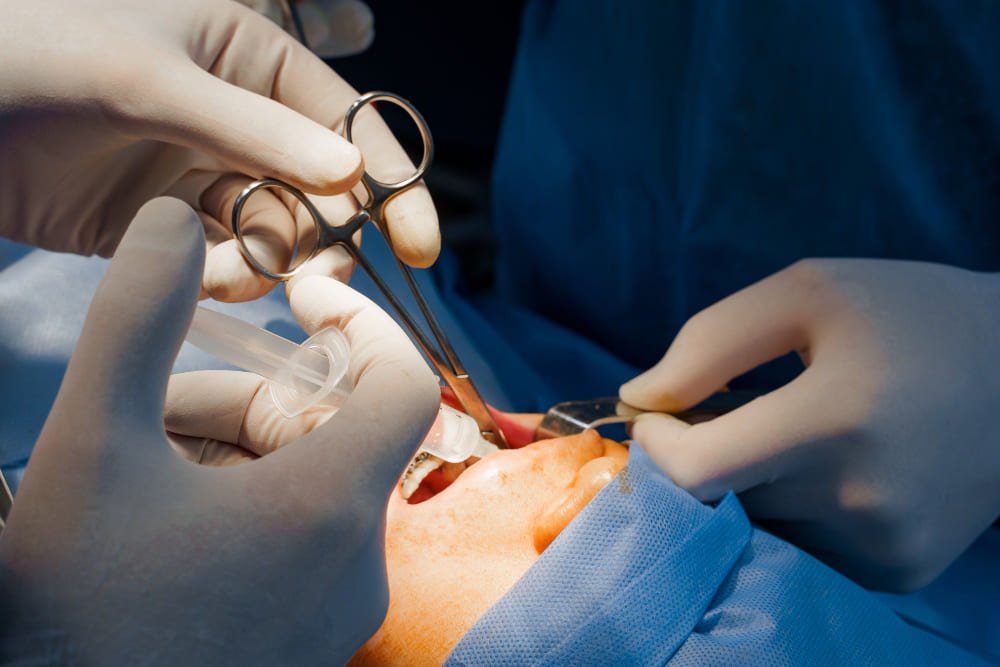

Servicios de Odontólogo en Villahermosa, Tabasco

Atención dental integral